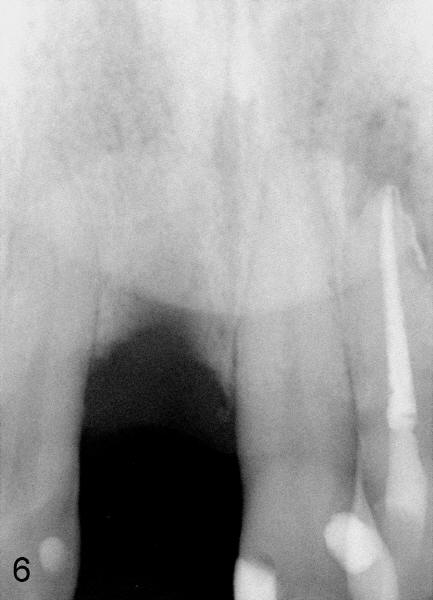

The patient is scheduled to return 1 week later for #8 socket debridement and irrigation.  The labial aspect has undergone atrophic changes (Fig.3,4).  More surprisingly is that the labial plate is found to be lost during socket debridement.  The labial plate seems to be intact at extraction.  Otherwise socket preservation must have been done.

Does this post-extraction infection happens often, but without being noticed?  Four quadrant scaling and root planing should have been conducted prior to extraction to reduce infection in this case. Note calculus in the lower anteriors (Fig.1).   Does immediate implant with bone graft prevent loss of the labial plate?   What should we do for this case now?  Wait for 2-3 months before implant placement?  Or bone graft after the infection is under control?

Your collagen plug may actually help open the pathways for infection. It keeps the wound open for too long. Nature always heals better than man made interruption..The bucccal plate is always a very thin bone and usually resorbs away during bone healing, These are all normal bone healing processes. But the protein matrix (granulation tissue) is always there to form the future new bone as the bone is re-mineralized. If you remove all the granulation tissue, You take away the matrix to form the new bone. In the future when you extract a tooth, don't put anything inside. Absolutely no suture (that may also cause infection too) unless it is for control bleeding. Natural blood clot will start the beautiful healing process and wait 3-6month, then you have nice healthy bone to work with. That is the reason I don't do immediate implant. For your case now, Just wait for 6 months, Then I would try to create a new buccal wall from the remaining lingual plate.  This is a very delicate procedure. If you want to, I can do the surgery while you assist and learn.  Joseph Lau, DDS 09/11/2011